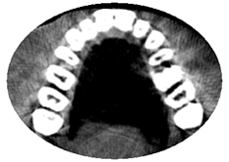

歯が骨の内側と外側の厚みの中でどこに位置するかがわかります。 デーモンシステムでは骨も外側へ拡大してくれますから、その変化はCT無しではわかりません。 |